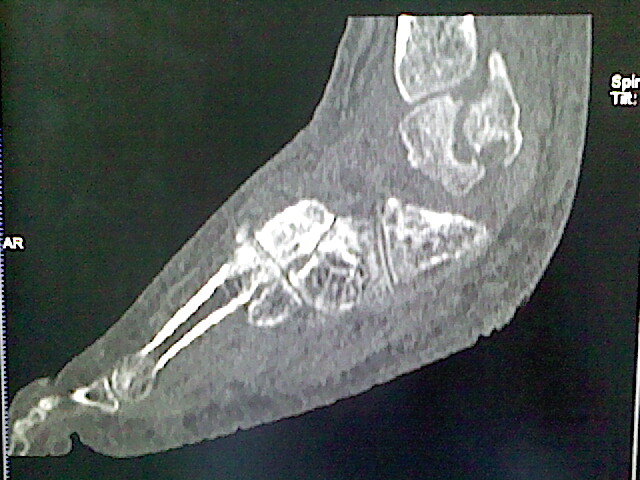

标题: CT16814:男,76岁,左小腿疼痛,不能站立 大家给看看 [打印本页]

男,76岁,左小腿疼痛,不能站立

本例骨质改变主要表现为滑膜或韧带区的骨侵蚀融解(胫腓联合区骨质破坏无硬化边),距骨后部骨质破坏区有硬化边及死骨样改变.所以,本例考虑关节结核可能性大,绒毛膜结节性滑膜炎多发于中年,且极少见于膝髋以外的关节,骨质硬坏也以压陷吸收为主,有明显的硬化边,骨膜增生呈结节状(可以mr鉴别),所以本例暂除外.

另不除外可引起相似表现的其他炎症如布氏杆菌性关节炎等